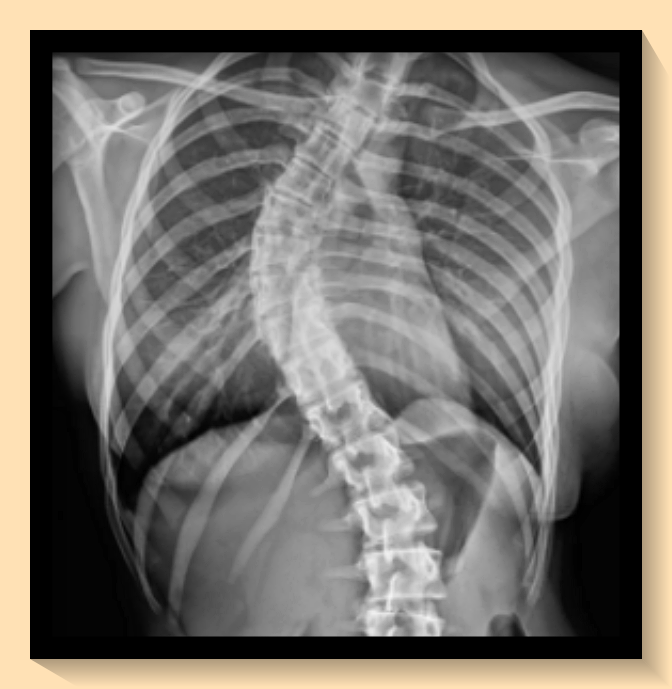

병역 신체검사에서 척추측만증의 판정을 이해하기 위해서는 '콥각도'라는 개념을 알아야 합니다. 병역 판정에 따라 등급이 달라집니다. 2024년부터는 20도 이상 40도 미만의 척추측만증 환자는 3등급으로 분류되어 현역 복무 대상이라는 새로운 기준이 적용되었습니다. 40도 이상의 경우에는 공익 판정을 받을 수 있습니다. 병무청에서는 X-ray 장비로 체크를 하지만, 병원에서 받은 서류를 준비해 가는 것이 좋습니다.

방사선 사진의 경우, CD 복사본으로 제출이 가능하며, 영상 자료 등은 비용 부담이 크다면 제출하지 않아도 무방합니다. 그러나 필요한 경우, 자료를 요구받을 수 있으니 척추측만증에 대한 정형외과 별도 기준을 확인하시는 것이 좋습니다.